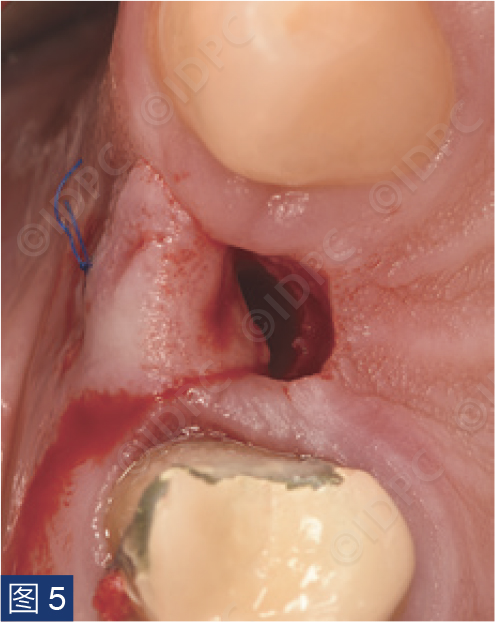

手术在局部麻醉(盐酸阿替卡因4% 1:100,000)下进行。行保留乳头的U形腭侧切口,翻全厚瓣并卷向颊侧(图5)。在皮瓣卷向颊侧的部分进行去上皮。这将弥补颊侧软组织缺损。逐级备洞,植入copaSKY 4 x 10种植体,植入扭矩30 Ncm(图6)。植体边缘放置在牙槽嵴顶下1 mm,以补偿未来牙槽嵴上方的软组织变宽(图7)。